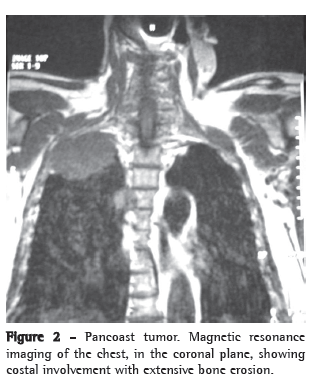

We report the case of a 49-year-old female patient, who worked as a maid in a rural area near the city of Dianópolis, Brazil. She presented a history of cough with purulent expectoration, which had intensified in the last four months. She also complained of unconfirmed fever and asthenia. She had received treatment for pneumonia with nonspecific antibiotic therapy in her town, however, with no clinical improvement. The patient reported having used a corticosteroid (prednisone), although not precisely reporting the reason, dose or duration of the treatment. She denied smoking, alcoholism, and was unaware of previous systemic diseases. Physical examination revealed good general health status, and pulmonary auscultation revealed the presence of crackling rales, mainly in the upper and posterior third of the right hemithorax. A high-resolution computed tomography scan of the chest, performed in November of 2006, showed consolidation in the anterior and posterior segments of the right upper lobe, with air bronchograms and interposed cavitation (Figure 1). In view of the clinical-radiological profile, she was submitted to a diagnostic fiberoptic bronchoscopy, which revealed purulent fluid within the tracheobronchial tree and an exophytic lesion with an irregular surface and yellowish color obstructing the bronchial lumen of the left lower lobe within the upper segment (Figure 2). The results of the biopsy of that lesion and the transbronchial biopsy of the posterior segment of the right upper lobe bronchus revealed the presence of septate hyphae with 45º dichotomous ramification, which are characteristic of Aspergillus sp. Direct testing and culture for acid-fast bacilli (Löwenstein-Jensen) and fungi (Sabouraud) of the bronchial lavage and bronchial brush samples were negative. No neoplastic cells were observed in this material. Blood workup, biochemical analysis and immunoglobulin levels were normal. Serology for HIV was negative. Based on the clinical, radiological and histopathological findings, a diagnosis of CNPA was made. Treatment was initiated with 200 mg/day of itraconazole, and significant clinical improvement was observed after twelve months of treatment.